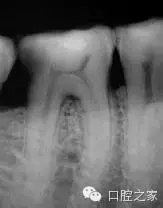

根管間的交通

近中根的形態(tài)與頰舌方向的寬度使得我們必須考慮到根管間的交通與峽部(圖4)。峽部(吻合)的定義是牙髓間的通道,在同一個(gè)牙根內(nèi)連接兩個(gè)或者更多個(gè)根管。在年輕患者身上,我們會(huì)期望發(fā)現(xiàn)較粗的根管,同時(shí)具有較寬的峽部。繼發(fā)性牙本質(zhì)的沉積貫穿于牙齒的整個(gè)發(fā)育成熟過程,這些大的交通被逐漸分割為小的交通,直到最后,在40歲以后這些交通出現(xiàn)的頻率會(huì)逐漸降低。

在文獻(xiàn)所回顧的1,615顆下頜第一磨牙當(dāng)中,50%的近中根和20%的遠(yuǎn)中根中會(huì)出現(xiàn)V型的峽部。V型峽部被認(rèn)為是兩個(gè)主根管之間真實(shí)的交通,或組織間的寬交通。因此,峽部的存在應(yīng)當(dāng)被認(rèn)為是一種常規(guī),而不僅僅是診治年輕下頜第一磨牙時(shí)的例外。

在牙髓治療過程中,正是因?yàn)榭紤]到這些不可進(jìn)入空間的消毒滅菌較為困難,我們應(yīng)當(dāng)將努力集中于提高根管化學(xué)沖洗的效能,利用目前我們所能獲得有效的根管沖洗系統(tǒng)。近期Von Arx指出峽部的識(shí)別、治療與消毒具有重要臨床意義;Von Arx發(fā)現(xiàn)在根管治療失敗需要進(jìn)行根尖手術(shù)的病例中,有29%的病例存在完整的交叉吻合。